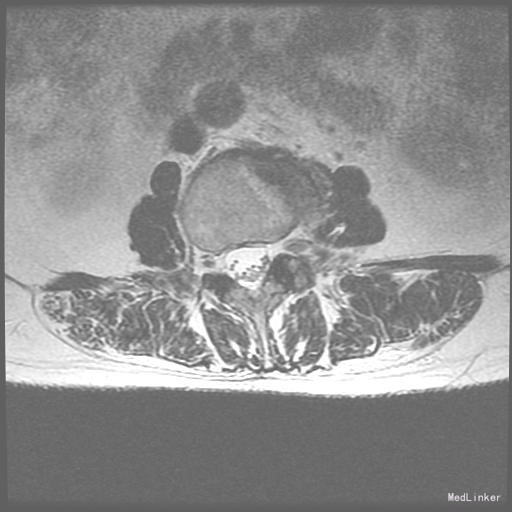

查体:脊柱无明显侧弯,腰背部无压痛,双下肢麻木酸痛,可牵连至脚跟。肌力肌张力可。腰部活动可,前屈后伸时感酸痛,无力。左侧直腿抬高试验阳性。 辅助检查:X线平片:腰椎侧弯前屈,L3椎体轻度滑脱,各椎间隙狭窄,腰椎退行性改变。 MRI:L4-5,L5-S1椎间盘膨出,L2-3,L3-4,L5-S1椎间隙狭窄,S2-3水平骶管内蛛网膜囊肿,腰椎序列不稳定,生理曲度局部后凸。

诊断:1 脊柱侧弯 伴不稳 2椎管狭窄 治疗: 前期微创腰椎侧路融合手术+后期 微创后路经皮内固定